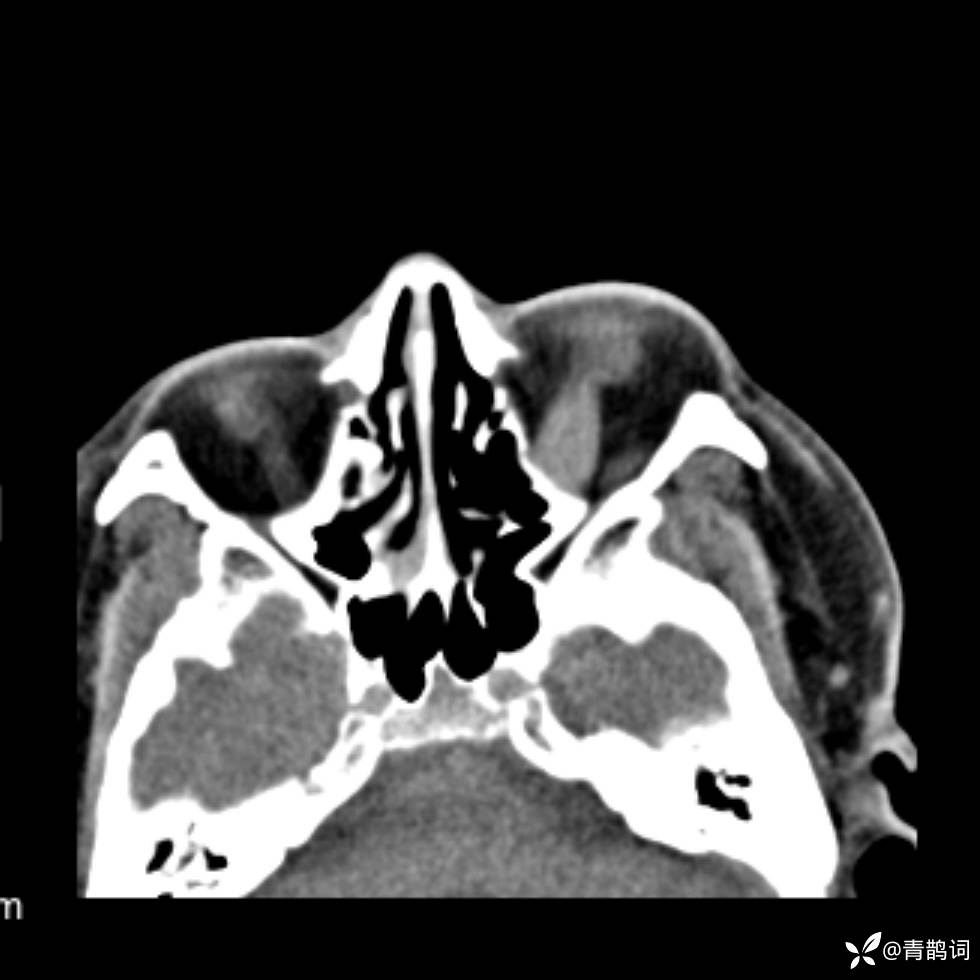

患者年龄:30岁。

患者性别:男。

简要病史:左颜面部肿胀2年,反复咳嗽咳痰,逐渐加重。

辅助检查

结合病史及影像学表现,期待评论区各位老师各抒己见~